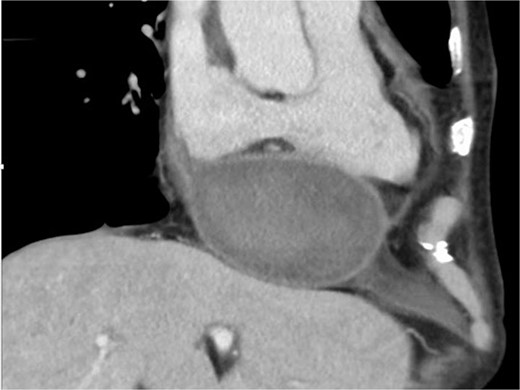

Intraoperatively, removal of the hematoma revealed that the pseudoaneurysm was secondary to LV rupture. The previously implanted pericardial patch broke, exposing a 5-mm rupture hole on the posterior mitral annulus. Thereafter, two pericardial patches were used to close the rupture from the inside (Fig. 3), and a repeat MVR (Epic 27 mm; St. Jude Medical, Saint Paul, MN, USA) was performed. The postoperative course was uneventful, and the patient was discharged 22 days later. One year after the second surgery, the patient has remained alive without cardiac events.

The two pericardial patches are used to close a 5-mm rupture hole under the posterior mitral annulus.